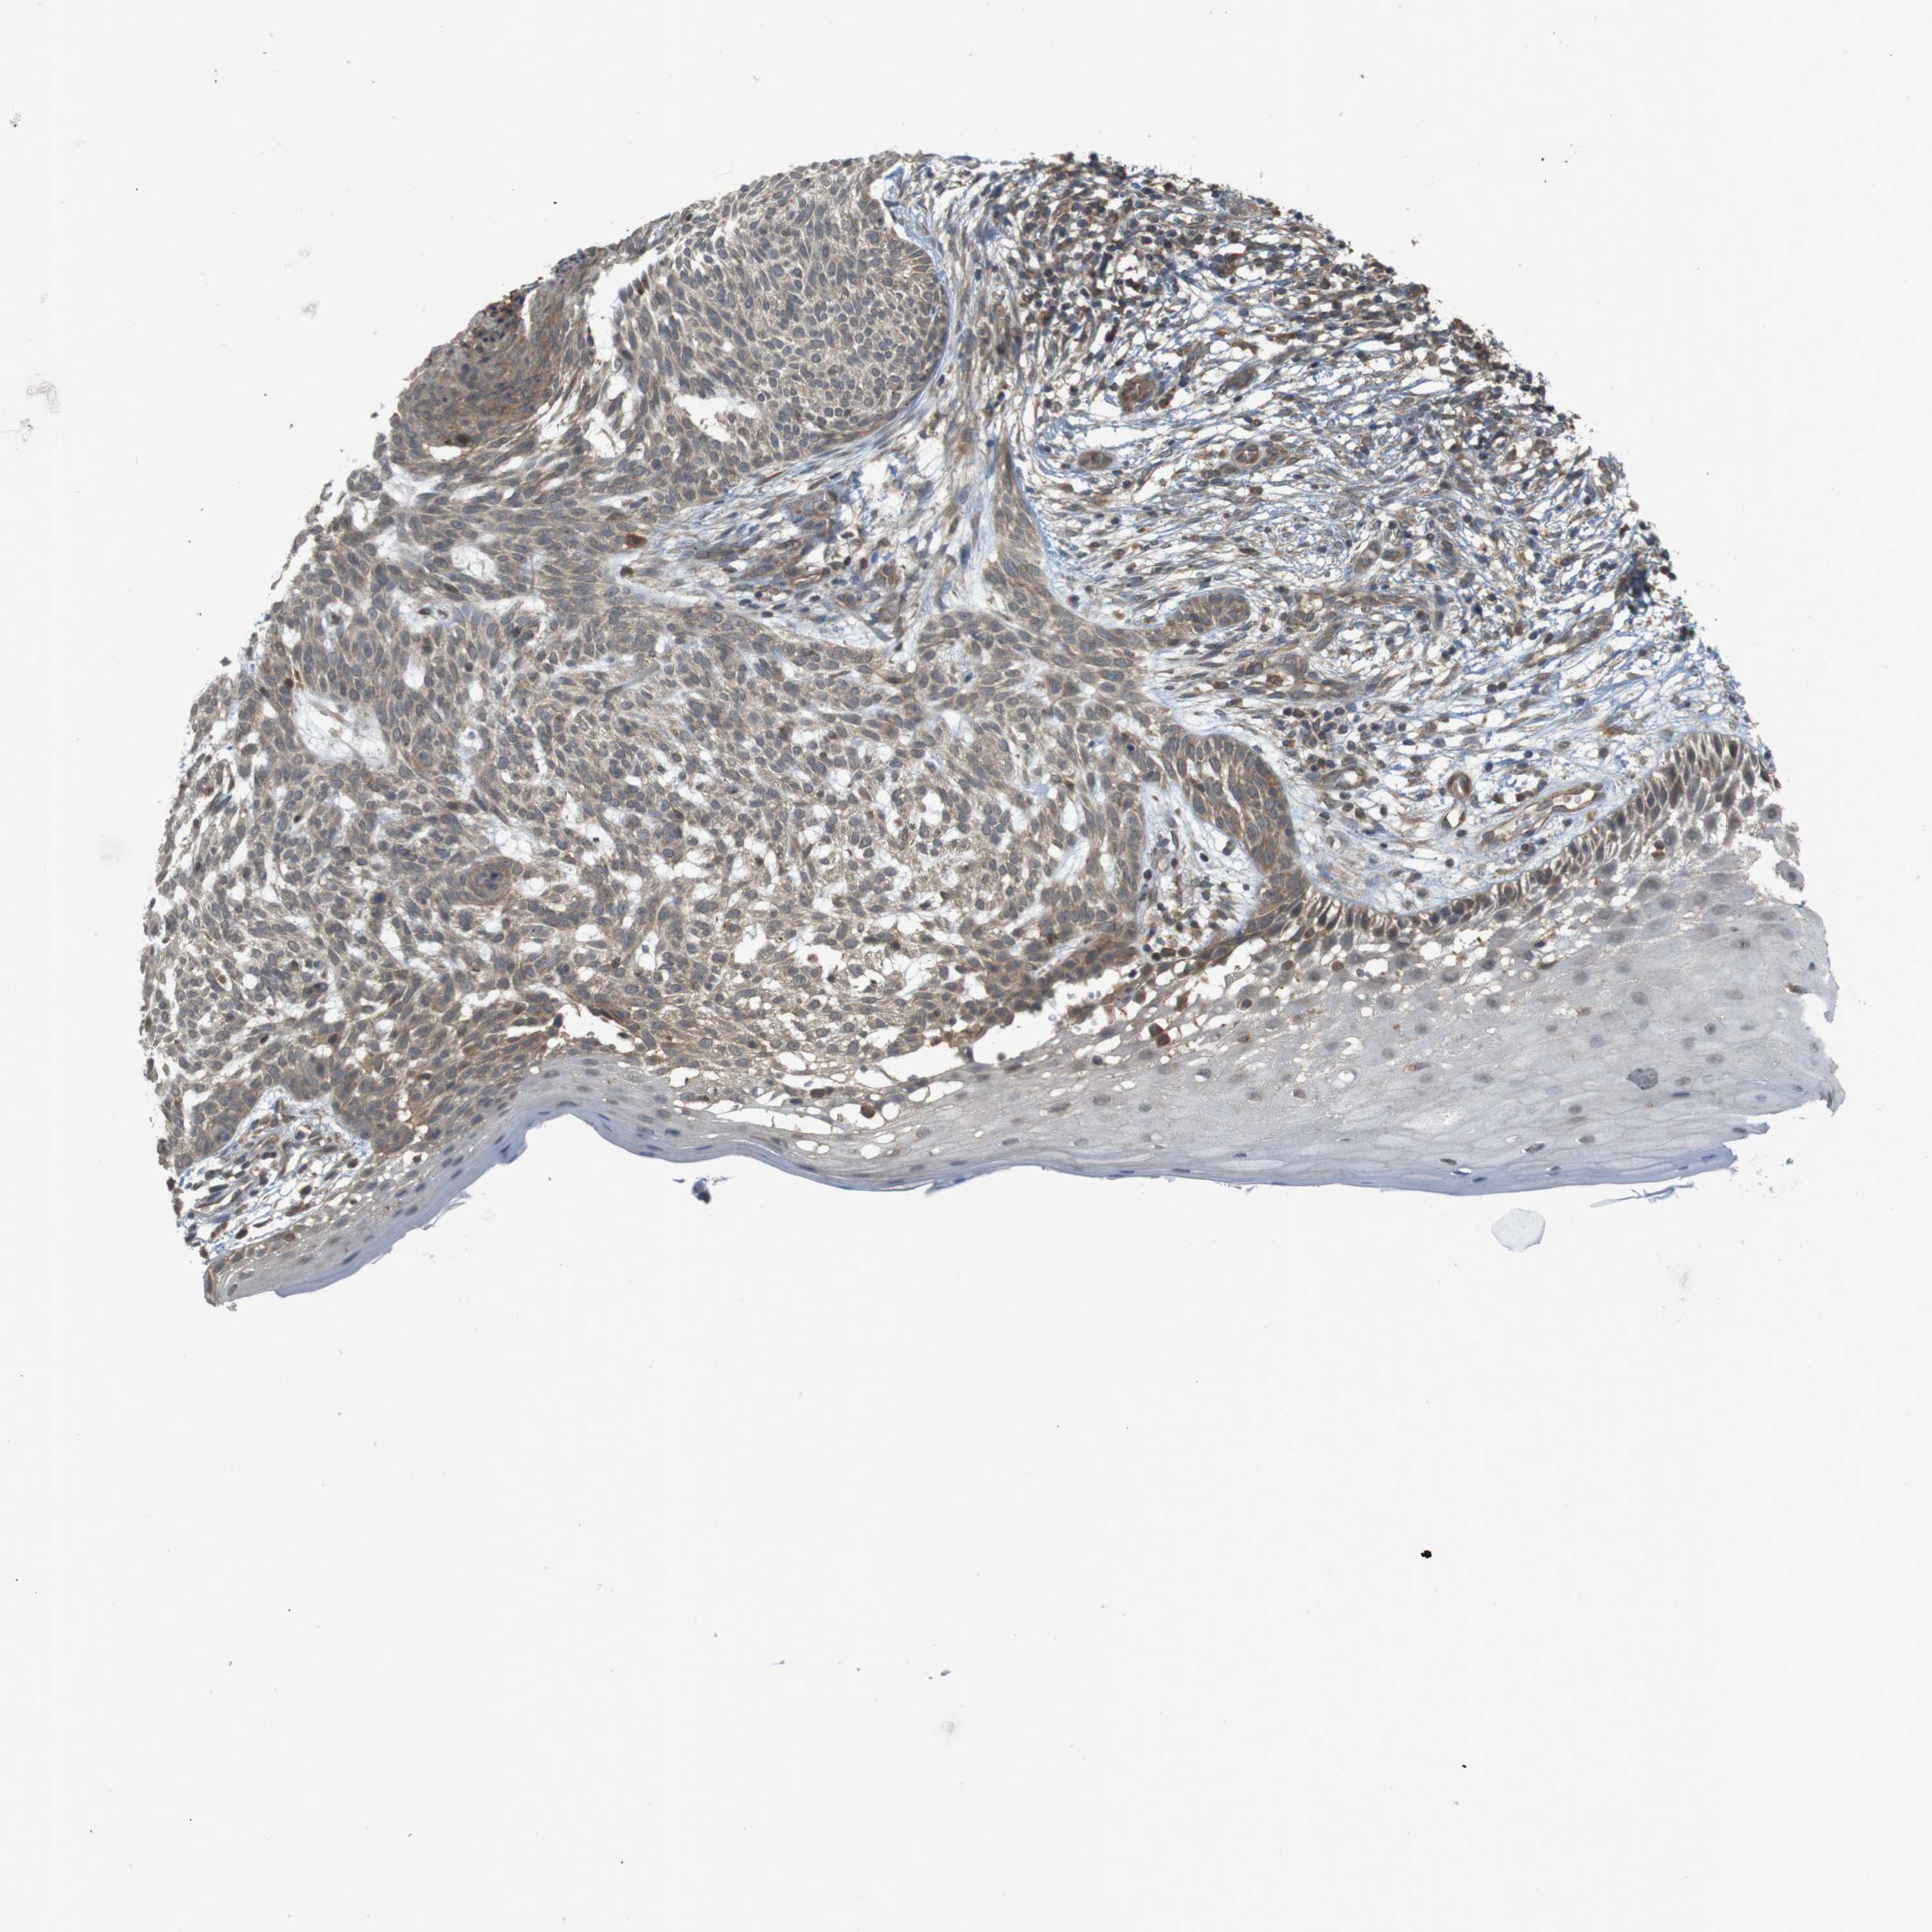

SKIN CANCER

Basal cell and squamous cell cancer